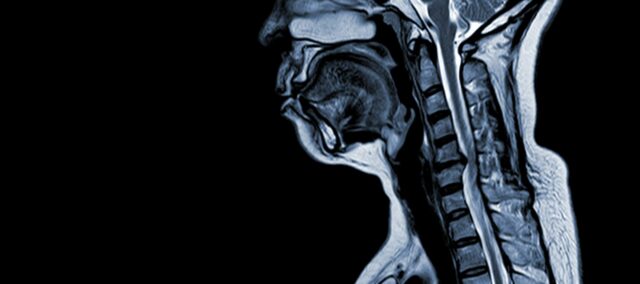

Cervikalna spondilotička mijelopatija (CSM) je neurološko stanje koje je vodeći uzrok ozljede leđne moždine u odraslih. Pojednostavljeno rečeno, radi se o kompresiji ili oštećenju leđne moždine u vratnom dijelu, prvenstveno zbog prirodnog procesa starenja koji zahvaća vratne kralješke. Pojam "mijelopatija" potječe od grčkih riječi "myelon", što znači "leđna moždina" i "patos", što znači "bolest".

Patofiziologija

- Degeneracija diska (ispupčeni disk) : CSM često počinje degeneracijom intervertebralnih diskova u vratnoj kralježnici, uzrokujući njihovo izbočenje ili stršenje u spinalni kanal.

- Subperiostalna formacija kosti (ventralno do spinalnog kanala) : Kao odgovor na povećani mehanički stres, tijelo formira novo koštano tkivo na prednjoj (ventralnoj) strani spinalnog kanala, potencijalno sužavajući prostor za leđnu moždinu.

- Osifikacija stražnjeg longitudinalnog ligamenta: Stražnji uzdužni ligament može doživjeti okoštavanje, otvrdnjavanje i kalcifikaciju, što pridonosi suženju spinalnog kanala.

- Hipertrofija ligamentum flavum: Hipertrofija ligamentum flavum uzrokuje njegovo zadebljanje i manje fleksibilnost, dodatno zadirući u prostor unutar kralježničnog kanala i kompresirajući leđnu moždinu.

Ove strukturne promjene zajedno dovode do kompresije i suženja spinalnog kanala, što rezultira simptomima i komplikacijama povezanim s CSM-om. Prepoznavanje ovih čimbenika rizika i razumijevanje uključenih patofizioloških mehanizama ključno je za prevenciju i liječenje. Rana dijagnoza i odgovarajuće intervencije ključni su za ublažavanje učinaka ovih strukturnih promjena na leđnu moždinu.